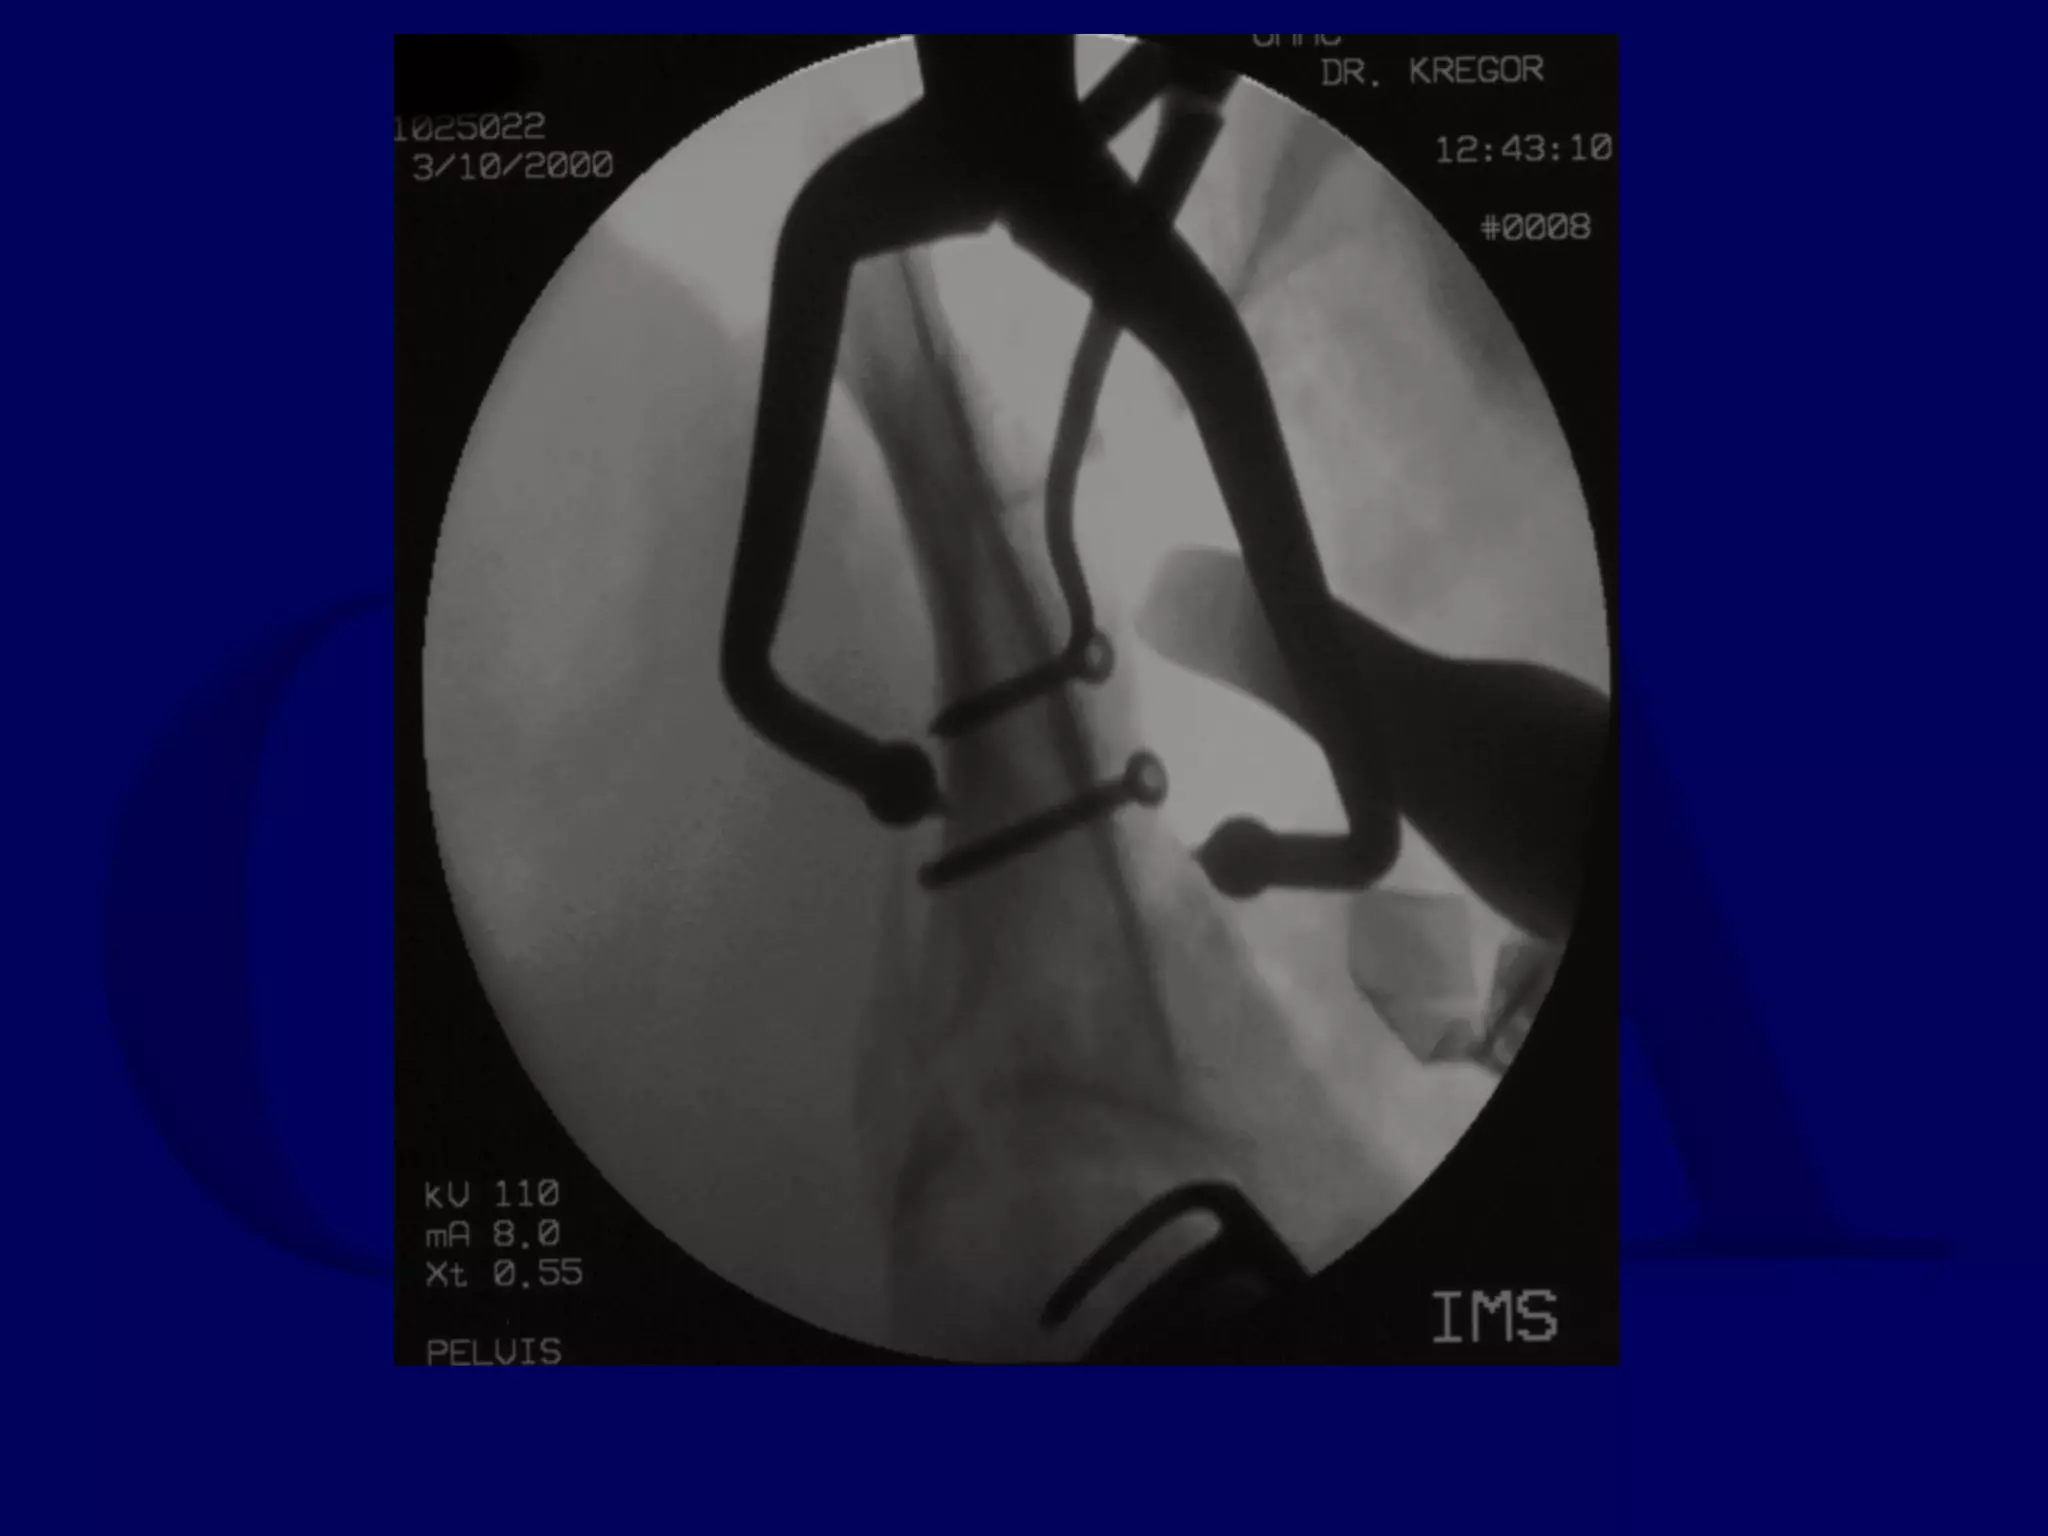

Special Case

“T-Type” Acetabular Fracture

Proximal Femur Fracture

14 y.o. Male

Sequential K-L / Ilioinguinal

Approaches

P.J. 00.12.16

Initial Kocher-Langenbeck

Approach

P.J. 00.12.18

Subsequent Ilioinguinal

P.J. 00.12.22